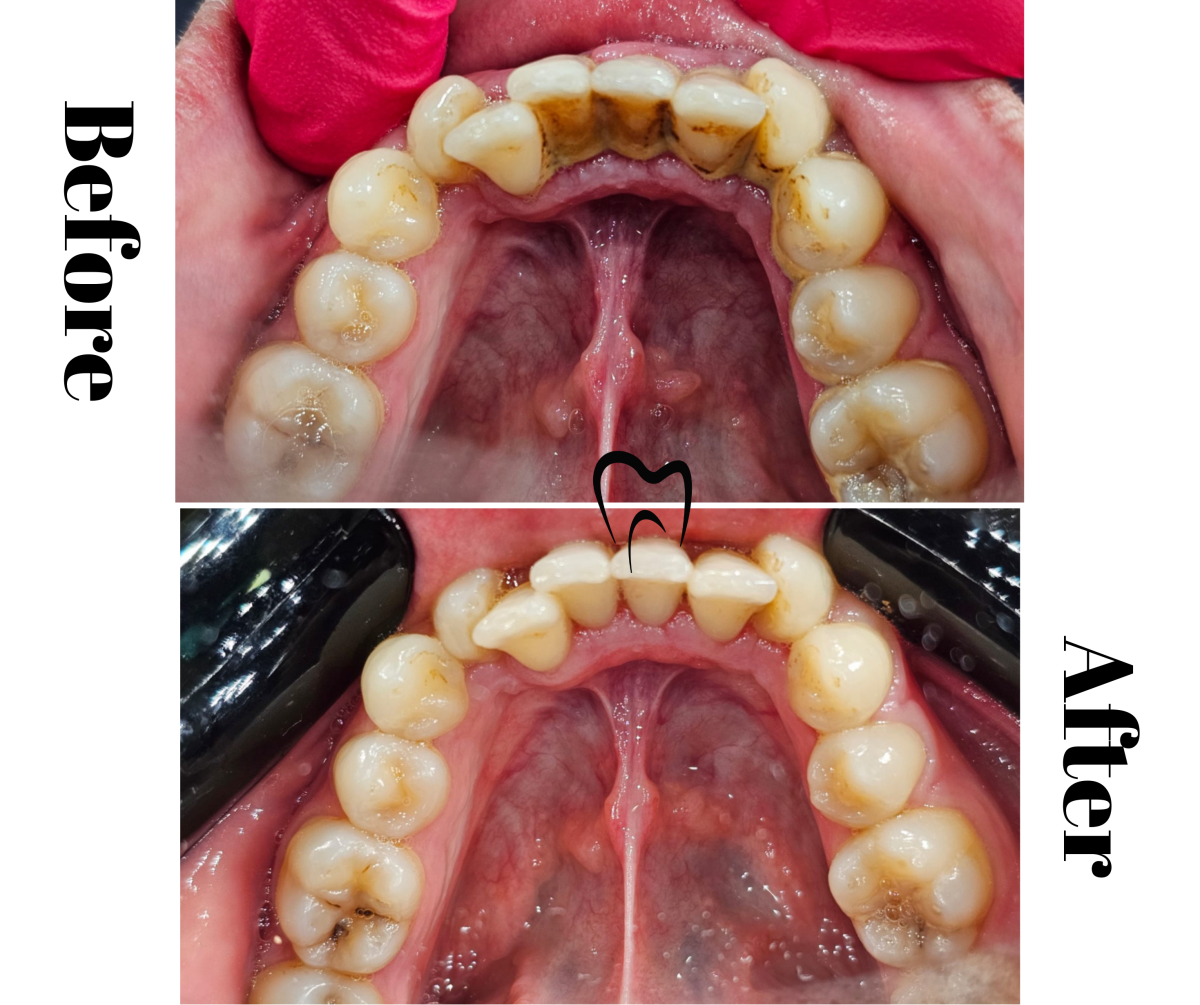

Lucrare ceramică pe suport zirconiu

Lucrare ceramică pe suport de zirconiu

Corane ceramică pe suport zirconiu